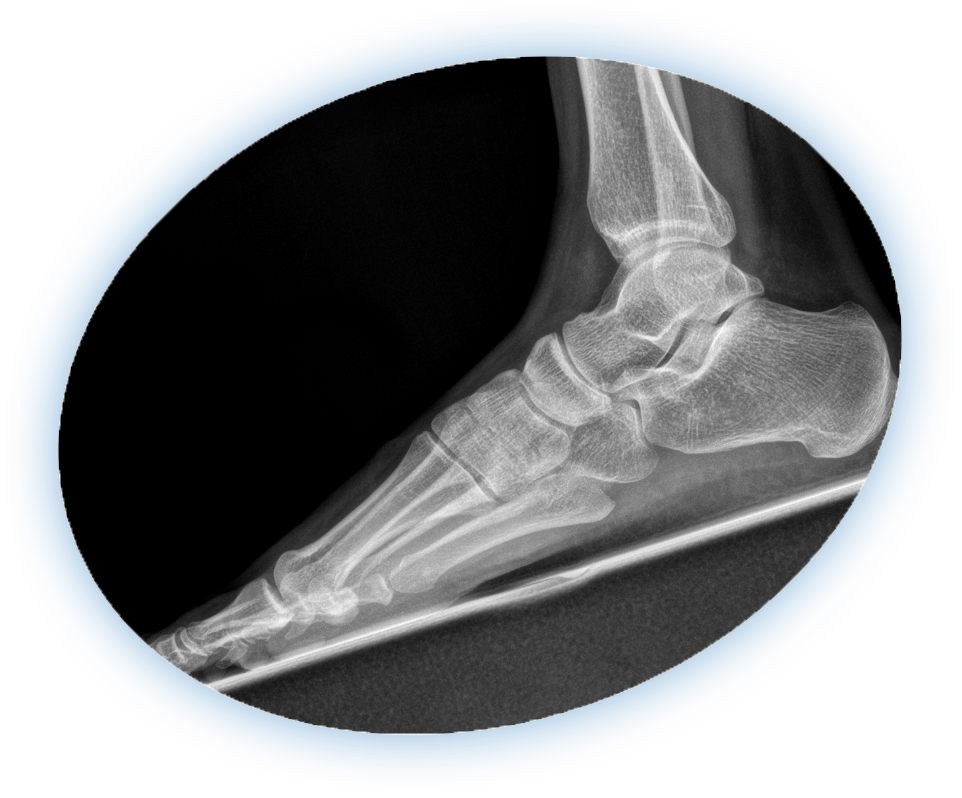

Flatfoot, also known as fallen arches or adult acquired flatfoot deformity, occurs when the arch of the foot collapses. This condition can cause pain, swelling along the inside of the ankle, and difficulty walking or standing for long periods. Over time, the deformity may worsen, leading to joint arthritis, tendon damage, and impaired mobility.

While conservative treatments such as custom orthotics, supportive footwear, and physical therapy can provide relief in early stages, advanced flatfoot often requires surgical correction to restore proper alignment and prevent progression.